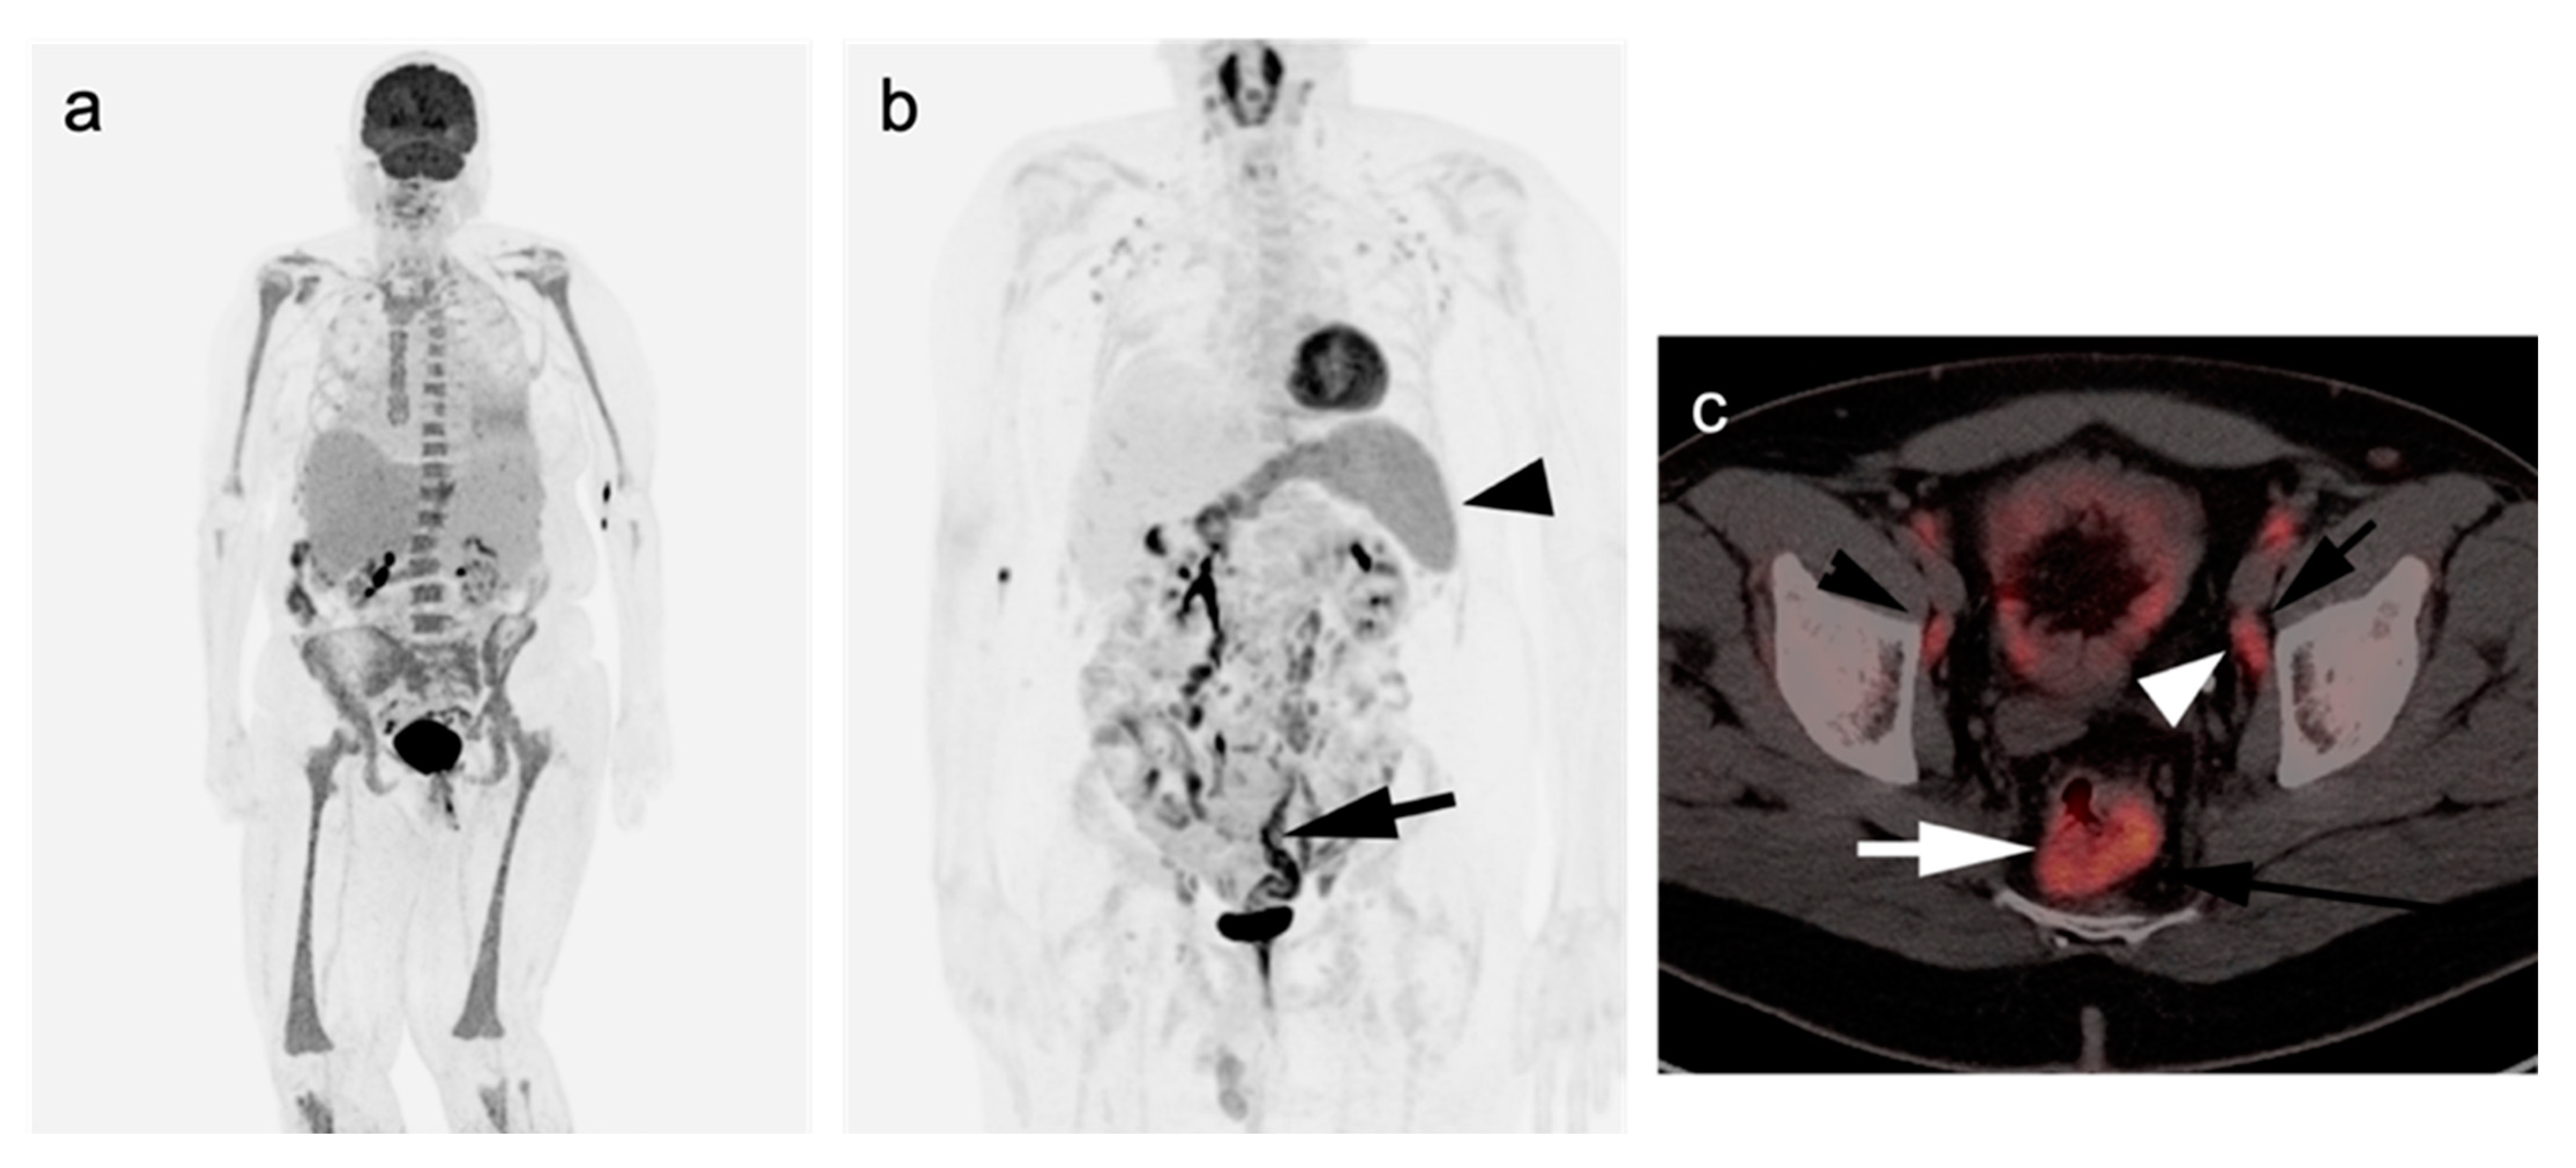

2.2.3. Baseline FDG PET-CT for Staging Lymphoma

- Kashyap, R.; Rai Mittal, B.; Manohar, K.; Balasubramanian Harisankar, C.N.; Bhattacharya, A.; Singh, B.; Malhotra, P.; Varma, S. Extranodal manifestations of lymphoma on [¹⁸F]FDG-PET/CT: A pictorial essay. Cancer Imaging 2011, 11, 166–174. [Google Scholar] [CrossRef]